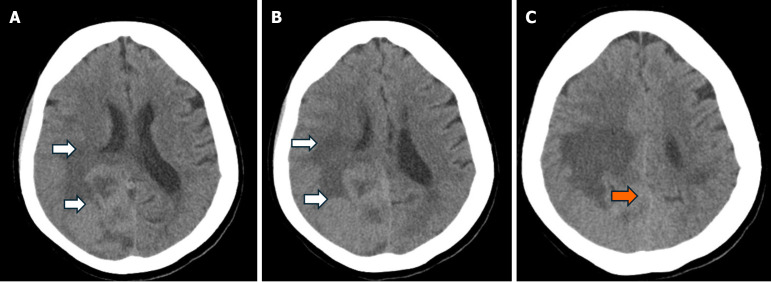

Case summary: We present a case describing a 78-year-old female who came in following a ground level fall. The primary assessment was notable for a history of similar recurrent falls and subtle left-sided peripheral visual field loss. Further neurological examination was otherwise largely unremarkable. A computed tomography scan of the head revealed a large extra-axial mass located along the posterior aspect of the falx. Follow-up magnetic resonance imaging confirmed a lesion measuring around 6.6 cm × 4.2 cm × 5.5 cm. A partial surgical resection of the right-sided portion of the lesion was performed. Complete resection was limited by insufficient visualization and challenges with hemostatic control of the left parafalcine region. Further histopathological analysis confirmed a fibrous meningioma with focal necrosis, consistent with World Health Organization Grade 2 classification. She was subsequently scheduled for outpatient follow-up to assess the residual tumor management.